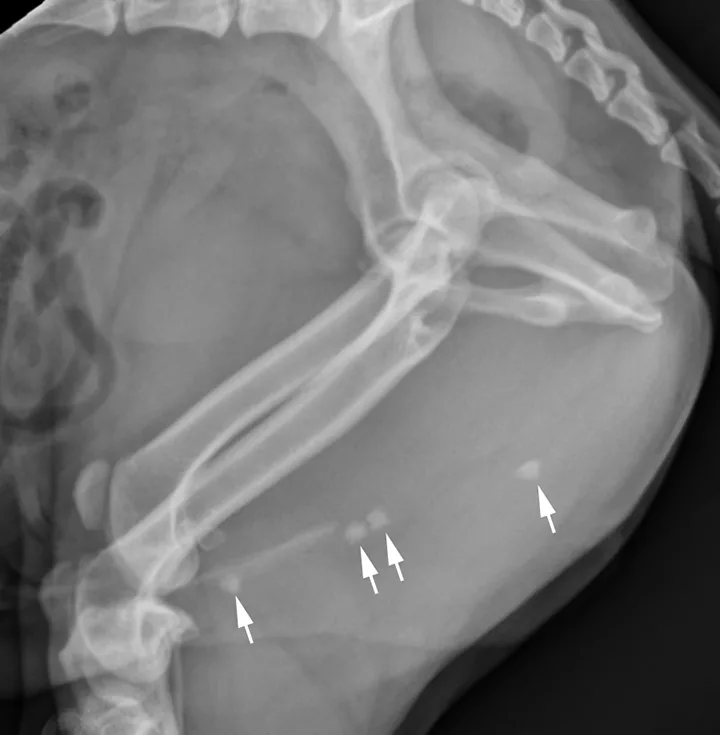

A separate center of ossification associated with the os penis may mimic a urethral calculus (Figure 11 A and B). A separate center of ossification can be seen at either end of the os penis and will be in line with the os penis. A calculus within the penile urethra would be seen ventral to the os penis in the location of the urethra. Contrast urethrography can be a helpful way to differentiate between a separate center of ossification and urethral calculus (Figure 11C).

FIGURE 11A

Lateral radiograph of a male dog collimated to include the urinary bladder and os penis. Note the well-defined mineral opacity just proximal to and at the same level as the base of the os penis—a separate center of ossification (arrow). Also note the two soft tissue opaque nodules summating with the prepuce, presumed to be small nipples (arrowheads).